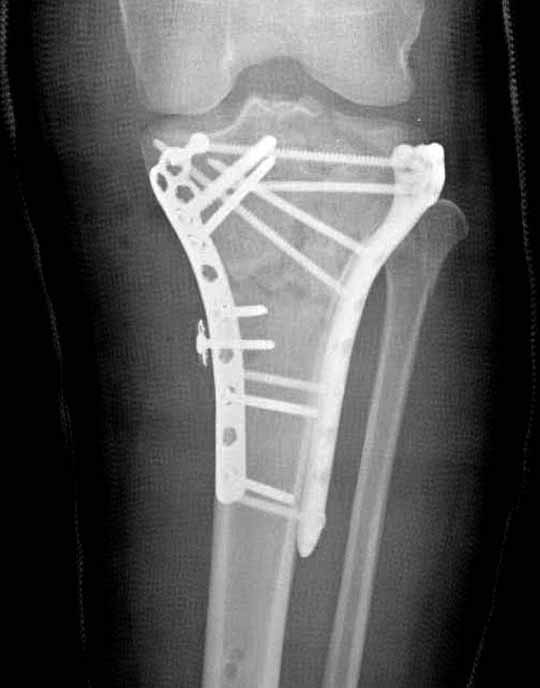

В приложении этапы фиксации Both Column Fx и пластиной Synthes для плеча при переломе медиального мыщелка.

Частая ошибка, когда фиксацию двух колонного перелома проводят одиночной пластиной, т.е с одной стороны, и такая фиксация не удерживает, происходит вторичноое смещение. Необходимо нейтрализовать второй пластиной или дополнительным наружным фиксатором.

Если у вас, кроме пластины, нет другого альтернативного варианта, тогда, учитывая мягкотканые проблемы с наружной стороны, я бы рекомендовал операцию делать в два этапа. Преимущества, сперва репозиция и фиксация перелома с медиальной стороны, а затем, после улучшения состояния мягких тканей, зафиксировать с латеральной стороны. Современные пластины имеют латеральный Jig для перкутанных мини доступов.

Для изолированных переломов медиального тибиал плато, фиксацию можно провести “медиальной пластиной”. Некоторые компании, например Smith & Nephew делают медиальные и медиально-задние пластины, но они мягкие, и легко можно создать нужный контур. Жесткость создается за счет фиксации жесткими пластинами, например экстра артикулярной пластиной для дистального плеча от Synthes. Медиальный доступ тоже не из легких, надо работать между pes and medial gastroc.